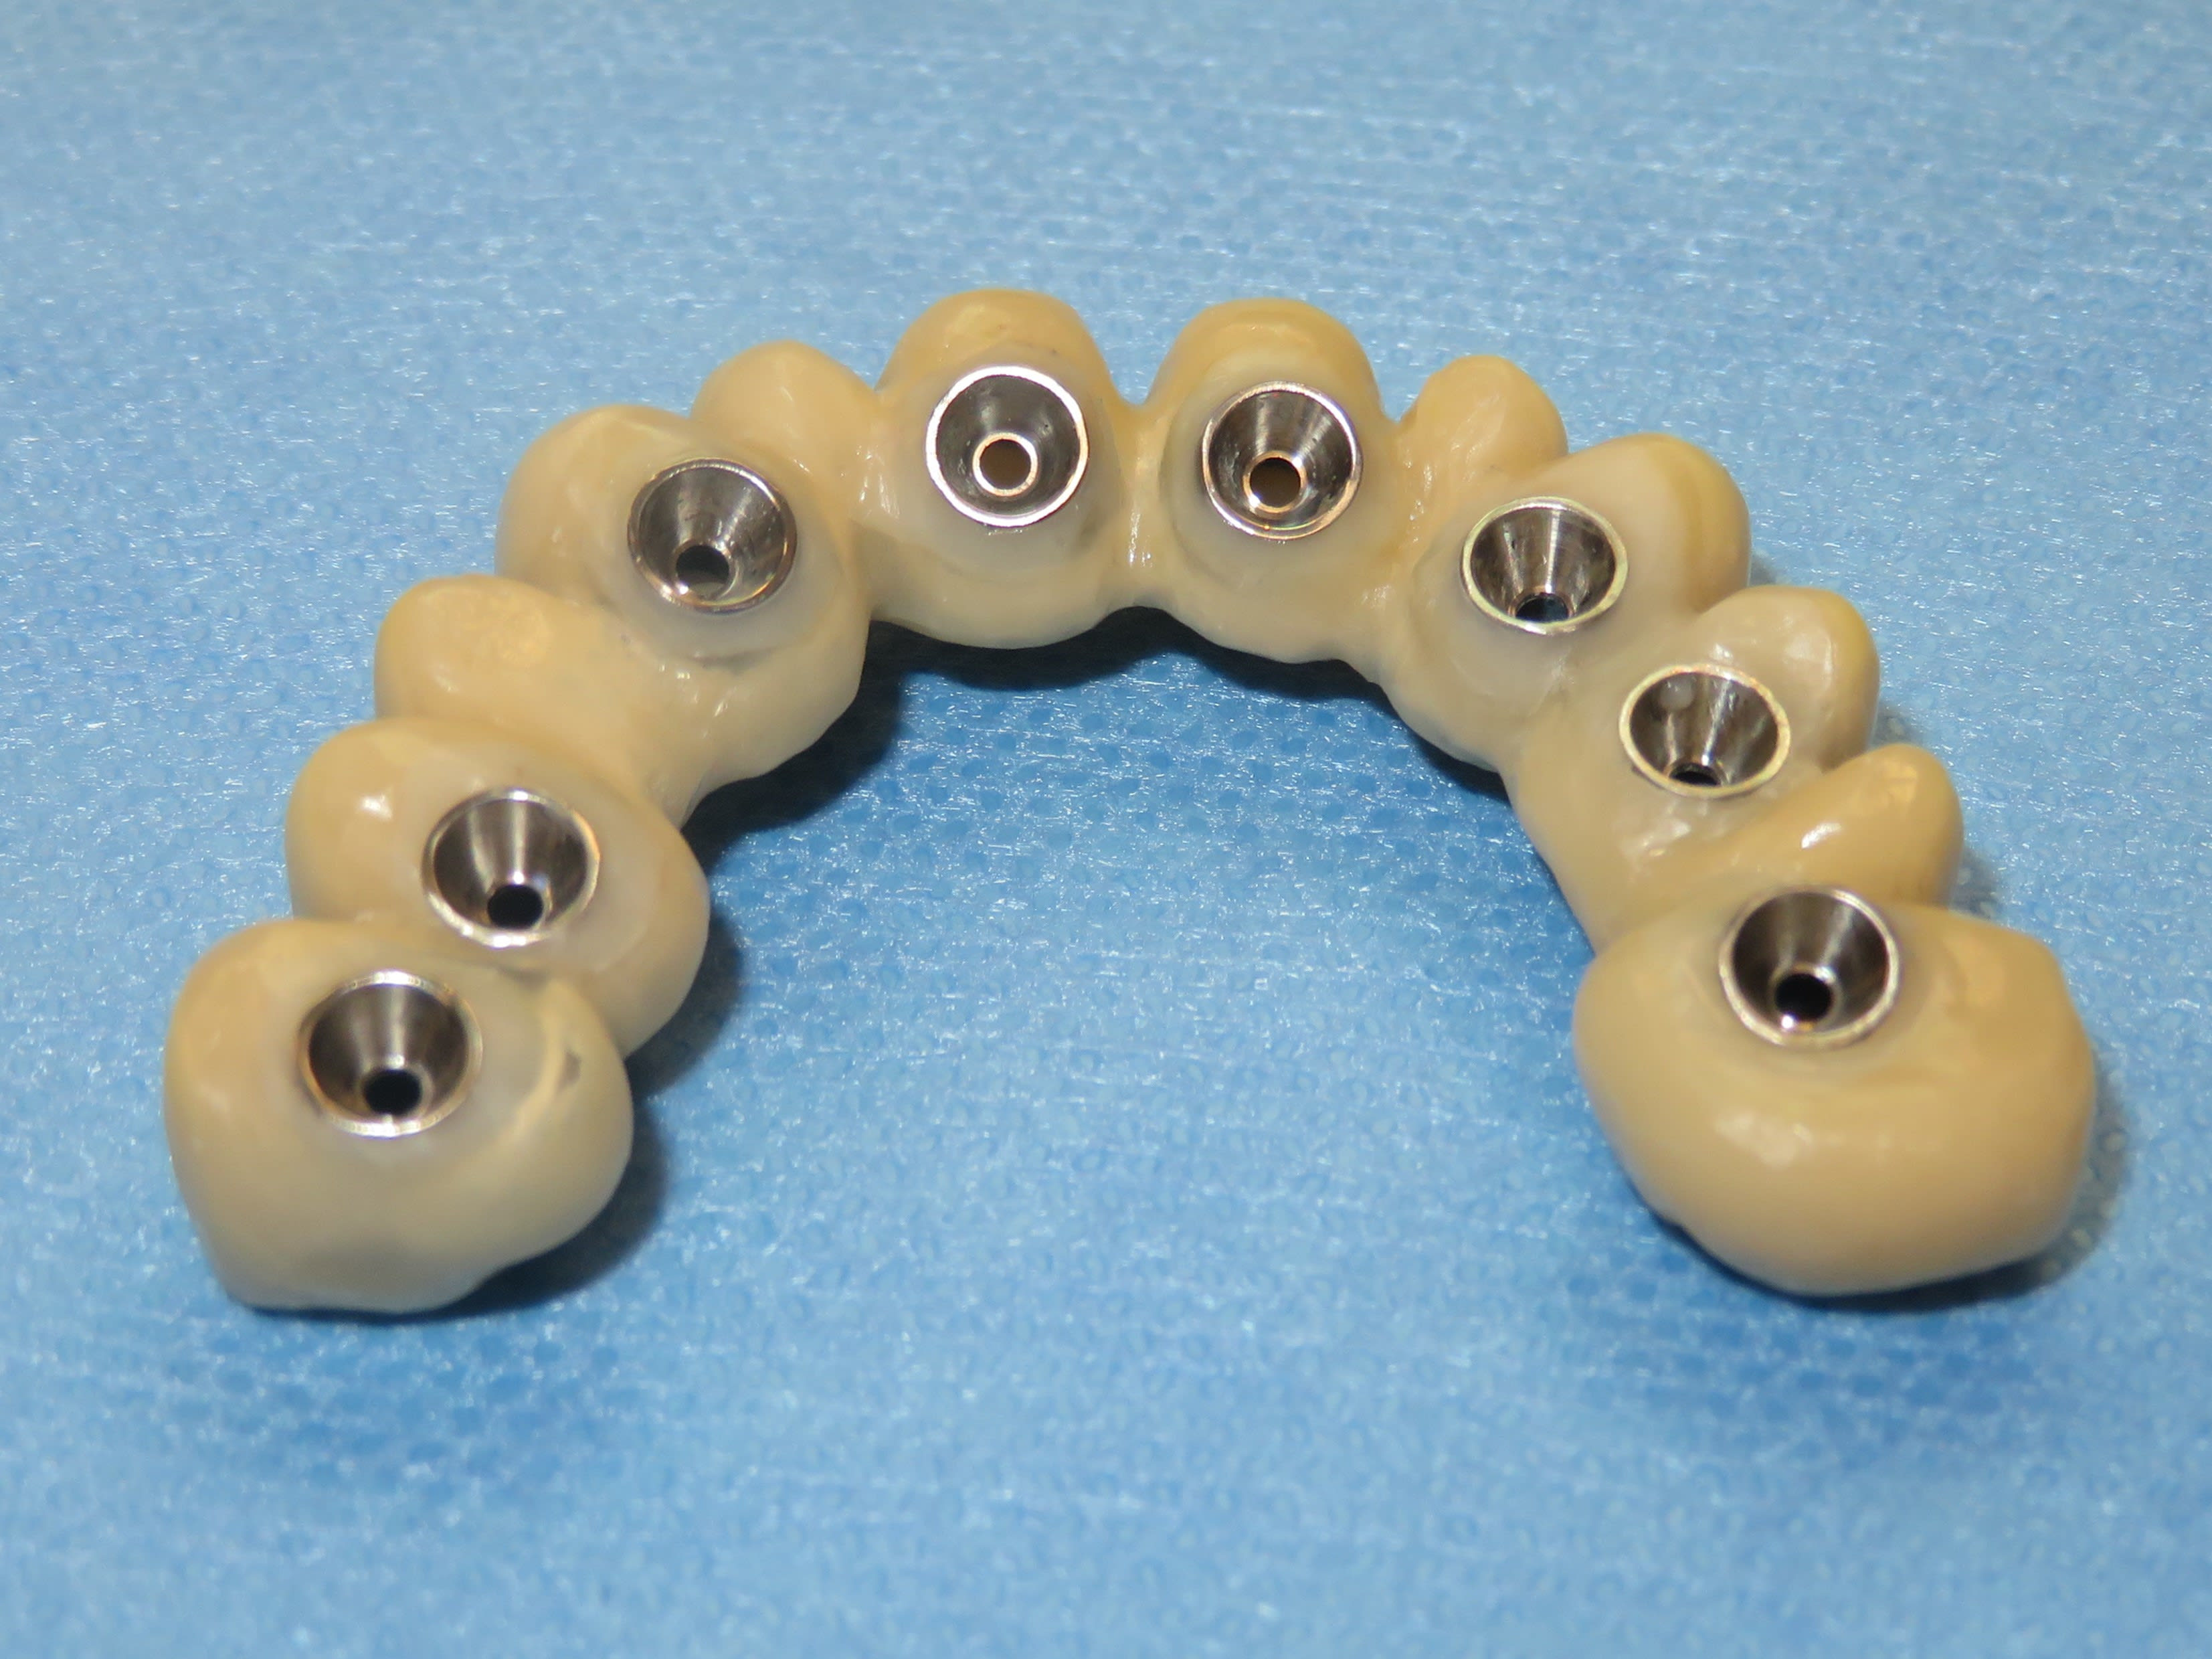

Je crois que la, il n’y a plus de doute . Full zircone avec rosenscrew, pas de tibase .

Le dernier bridge posé avec ce protocole